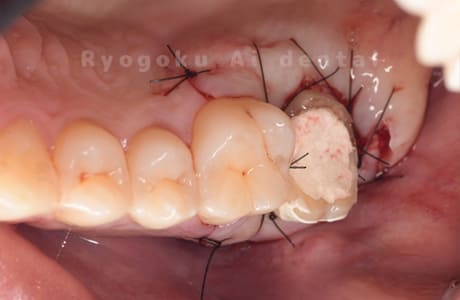

Case09

-

- 原因

- 左上6番重度カリエス

- 治療内容

- クラウンレングスニング

- 治療費用

- 44,000円(根管治療、補綴は別途費用)

他院で抜歯と判断された歯です。クラウンレングスニングを行い、保存を試みました。現在も問題なく被せ物が入り、使用できてます。

<リスク・副作用>

手術後は痛み、腫れ、痺れ、青あざなどの副作用が生じます。痛みは痛み止めを処方しますが、腫れ、青あざは1週間程度生じる場合があります。また、部位によっては神経の走行が複雑で、痺れが残り、長期的にお薬を処方する場合があります。